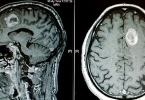

颅内胶质瘤是一种可能严重影响生活质量的疾病,应保持警惕并及时关注相关症状如不明原因的头痛、恶心、视力障碍等。当出现疑似症状时,应尽快就医,通过影像学检查及组织病理学确诊,并根据具体情况制定治疗方案,以提高康复几率和延长生存时间。